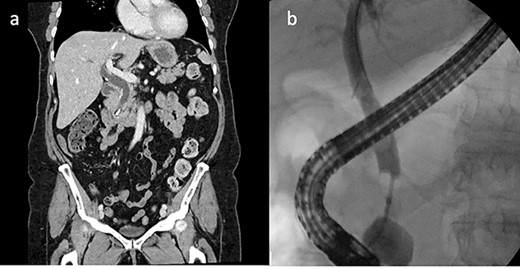

She was then referred to a larger tertiary center for spyglass cholangioscopy that enabled the surgeon to directly visualize the pathology within the bile duct. They found two surgical clips with a surrounding 30-mm stone impacted in the distal CBD. Electrohydraulic lithotripsy was used to divide the stone into smaller fragments, which were retrieved via balloon/basket extraction (Fig. 2). She was then admitted for 5 days and discharged once her liver function tests (LFTs) had stabilized.

ERCP with spyglass cholangioscopy. (a) Bile duct stone obstructing CBD. (b) EHL fragmentation of stone. (c) Two Surgical clips freed from stone material. (d) Biliary tree swept with balloon and basket.